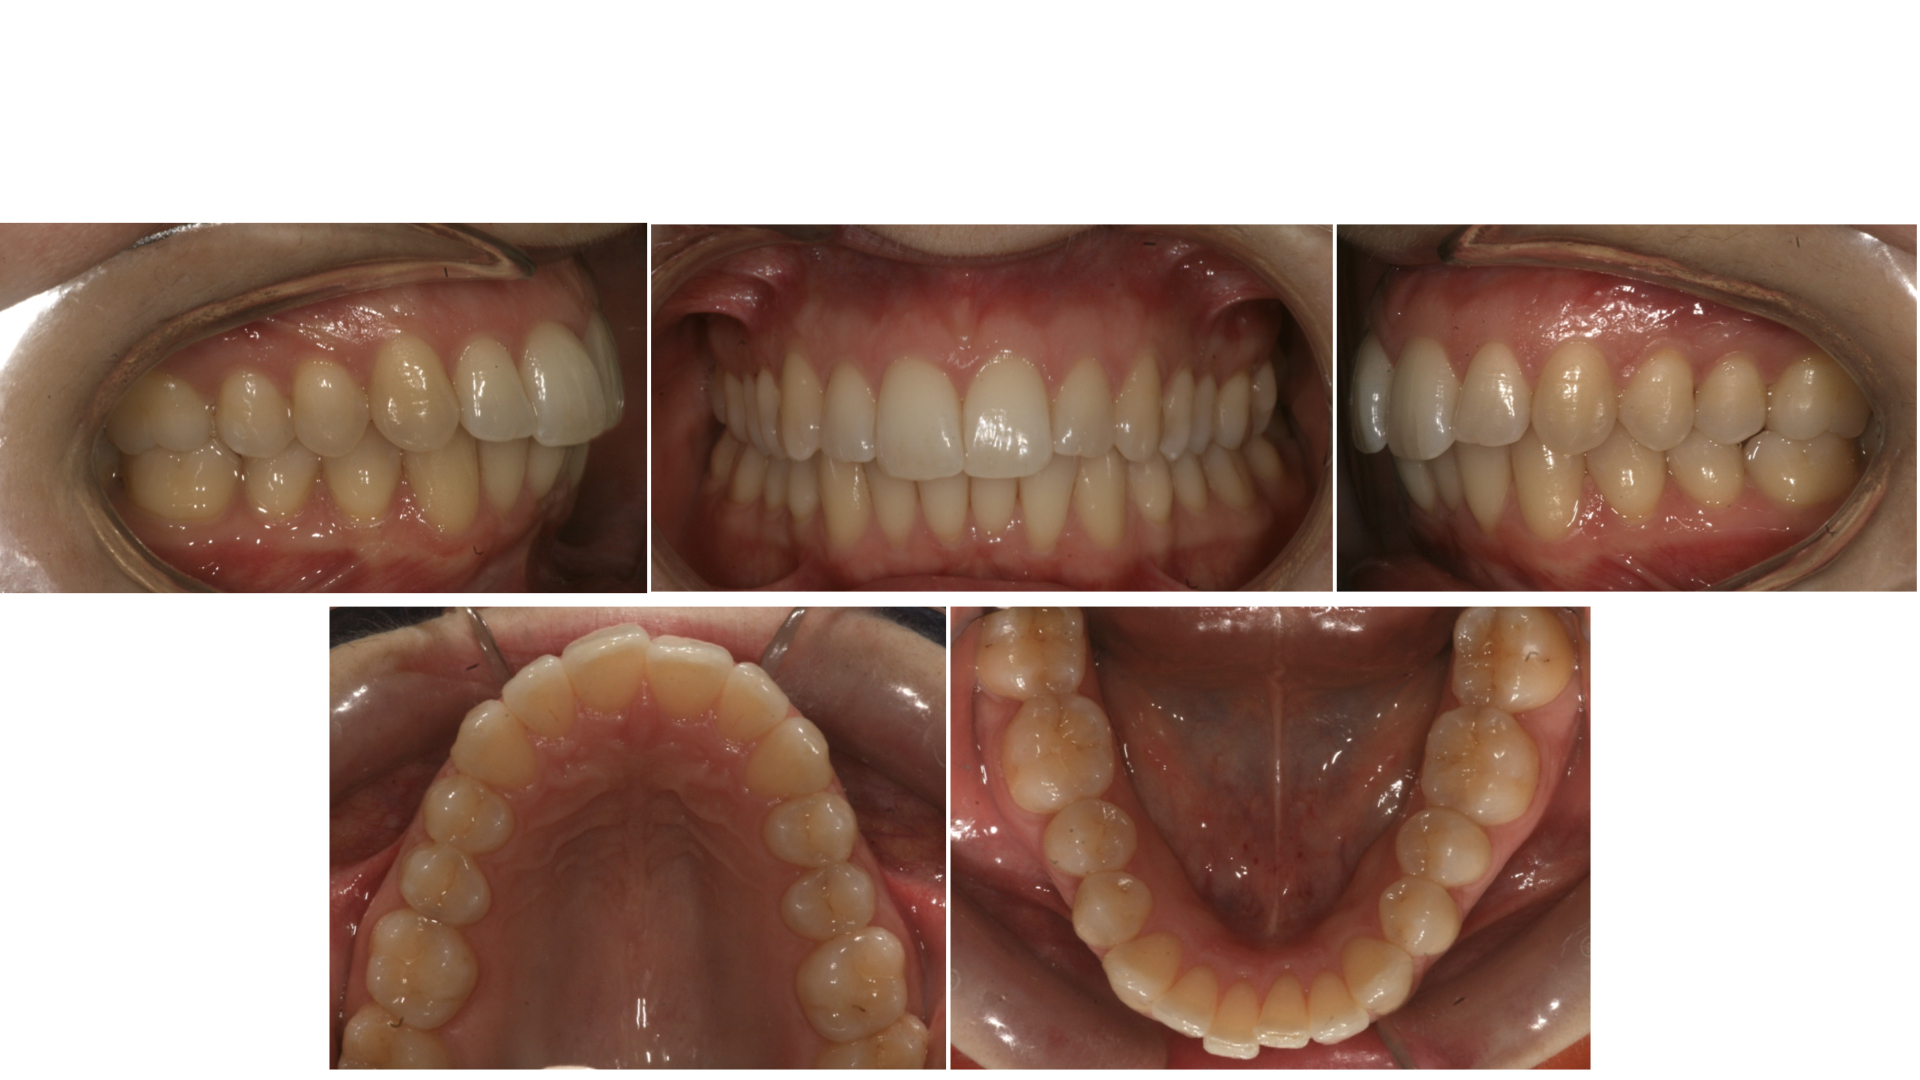

La paziente (37 anni) si è presentata alla nostra attenzione per la risoluzione dell’affollamento anteriore superiore ed inferiore (Fig. 1).

Fig 1. Fotografie intra-orali inziali.

Nel primo ciclo di stampa, sono stati stampati 5 allineatori diretti superiori ed inferiori che, nel caso in questione, hanno permesso la risoluzione dell’affollamento come previsto dal set-up in circa 2 mesi (Fig. 11 e 12).

Fig. 11. Fotografie intra-orali finali.